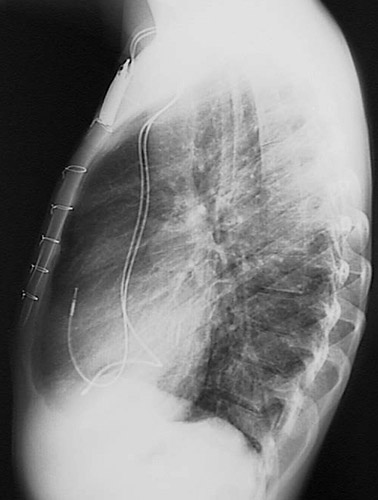

| This lateral chest radiograph demonstrates the presence of a cardiac pacemaker battery implanted under the skin of the upper left chest wall. The leads from the battery extend down to the right atrium and the apex of the right ventricle. Note the wires that closed the sternotomy incision are evident. |